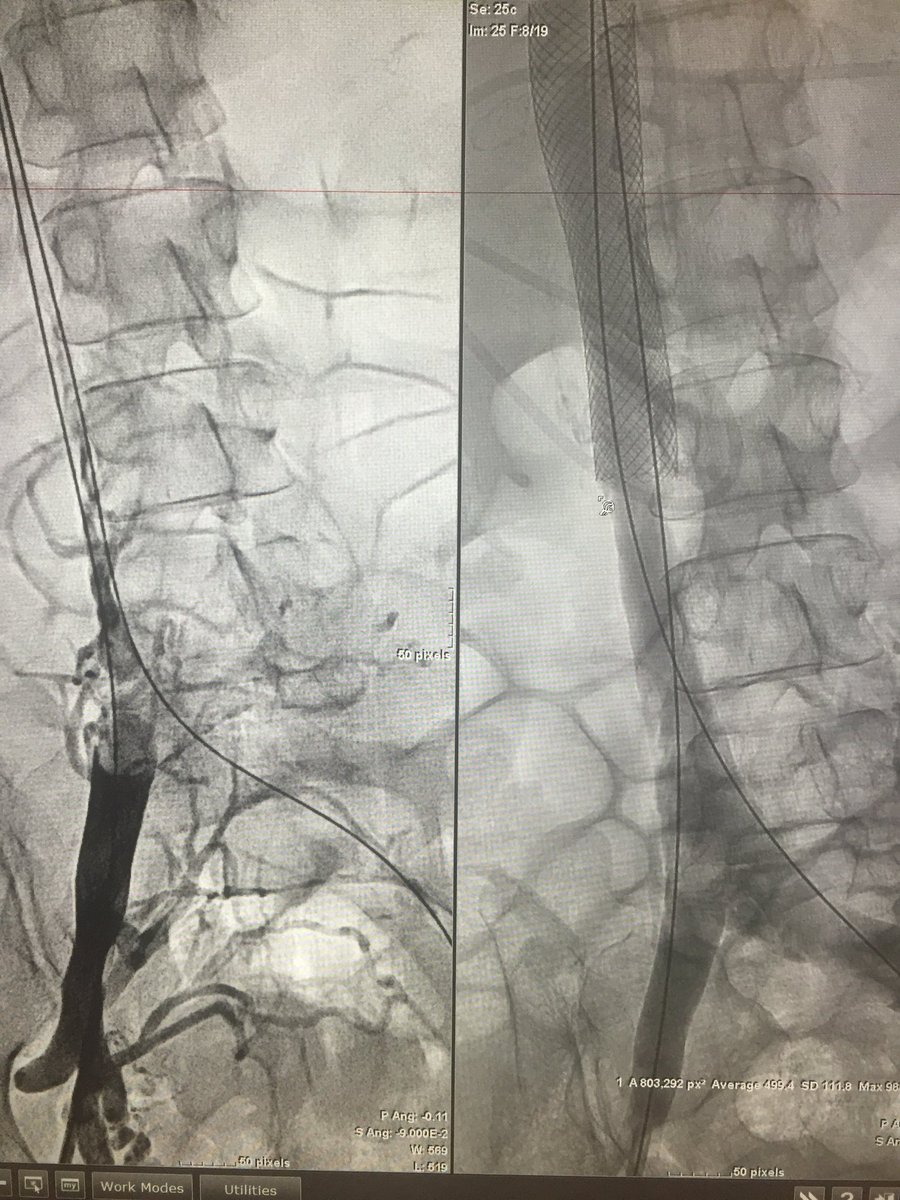

#DVT. IVC thrombosis. Single Session Endovascular Tx. #zelante Mount Sinai IR Jeff Mirviss Endovascular Today